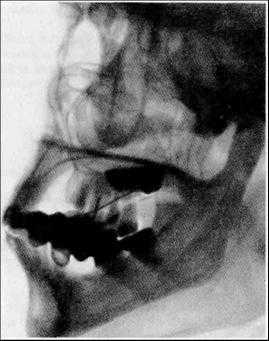

Методы рентгенодиагностики в стоматологии

Рентгенологические методы исследования являются ведущими в диагностике заболеваний челюстно-лицевой области, что обусловлено их достоверностью и информативностью. Методы рентгенодиагностики нашли широкое применение в практике терапевтической стоматологии (для выявления заболеваний пери- и пародонта); в ортопедической стоматологии (для оценки состояния сохранившихся зубов, периапикальных тканей, пародонта), что определяет выбор ортопедических мероприятий. Востребованы рентгенологические методы и челюстно-лицевой хирургией в диагностике травматических повреждений, воспалительных заболеваний, кист, опухолей и других патологических состояний.

3. Внеротовые (экстраоральные) рентгенограммы.

Внеротовые рентгенограммы дают возможность оценить состояние отделов верхней и нижней челюстей, височно-нижнечелюстных суставов, лицевых костей, не получающих отображения или видимых лишь частично на внутриротовых снимках.

Рентгенографию тела и ветви нижней челюсти в боковой проекции проводят на дентальном рентгенодиагностическом аппарате.

Проводится также и боковая панорамная томография, на боковом панорамном снимке одновременно отображаются зубы верхнего и нижнего ряда каждой половины челюсти.